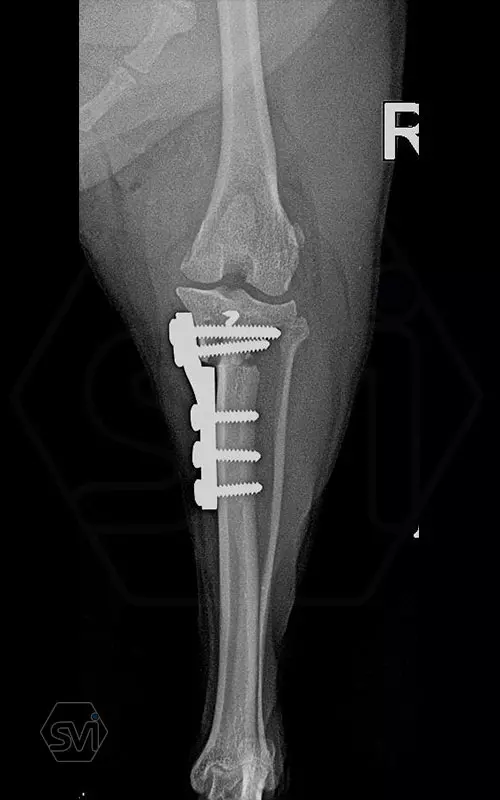

Mini TPLO-M plate:

non-locking, symmetrical, with 2.2 mm terrace (degree of shift), for standard 2.0 mm AO cortical screws (1.5 and 2.4 mm screws can also be inserted), material steel. Optimized for R12 blades.

Between October 2020 and December 2021, we performed 19 TPLO-M surgeries at the Animal Hospital in Nyíregyháza,: 16 times used the mini (2.0 R12) and 3 times the small (2,4 R15) TPLO-M plate.

The experience is very encouraging, we find the system and plates suitable for the simultaneous treatment of MPL and RACL. ( in case of 4/4 pat. lux. also). We will back soon with details.